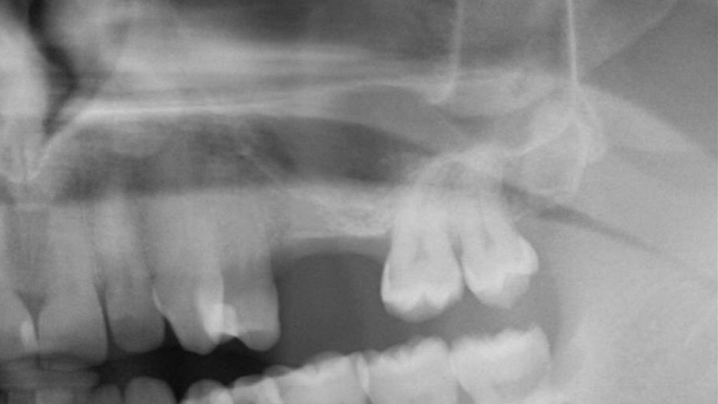

Clinical case: Delayed implant placement: sinus floor elevation by means of lateral

approach & implant placement with GBR

- Courtesy of Dr. Irfan Abas, Netherlands -